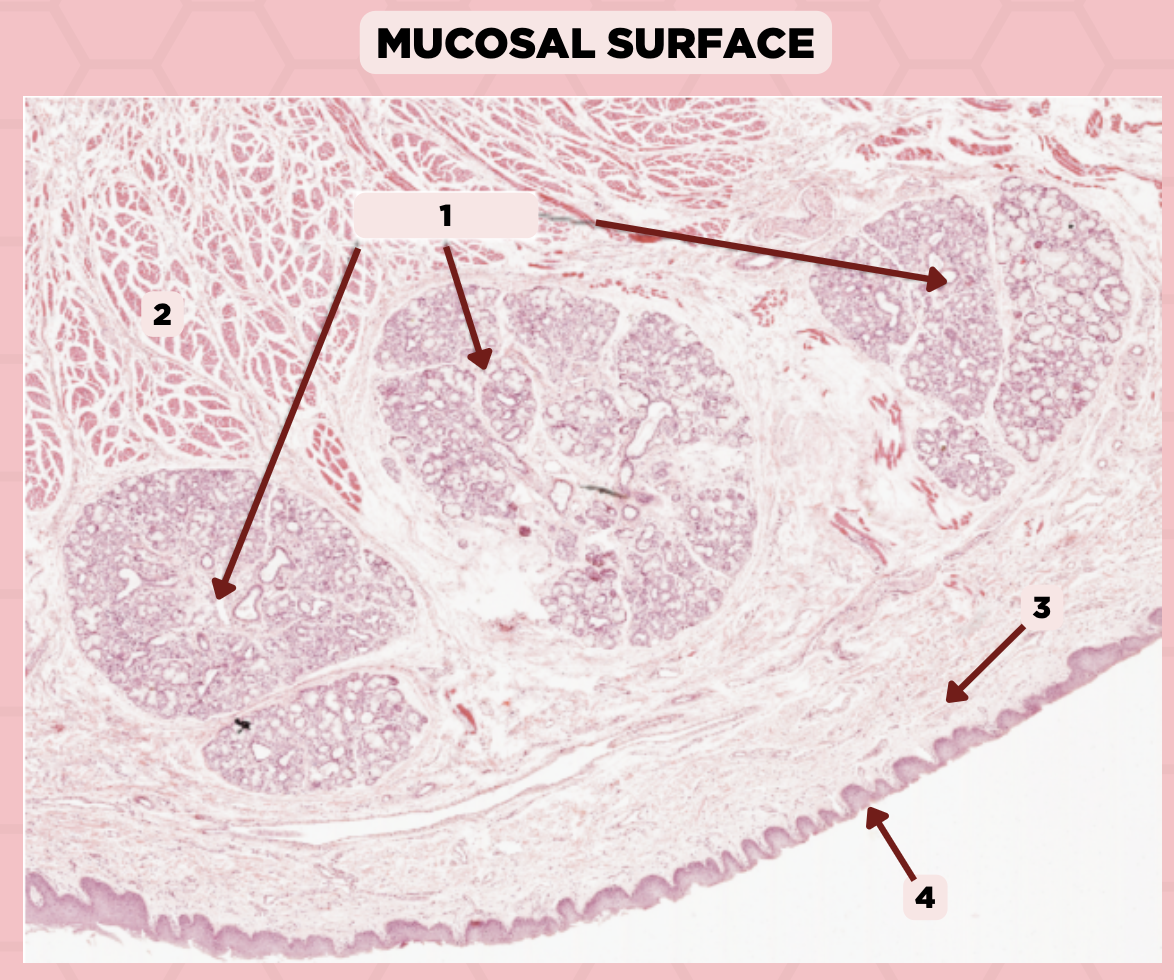

Lip

What specimen is showed in the picture?

Labial Glands (in the Mucosa)

Identify the structure labeled as 1.

Skeletal Muscle Cells

Identify the structure labeled as 2.

Lamina Propria

Identify the structure labeled as 3.

Mucosa

Identify the structure labeled as 4.

Lip

What specimen is showed in the picture?